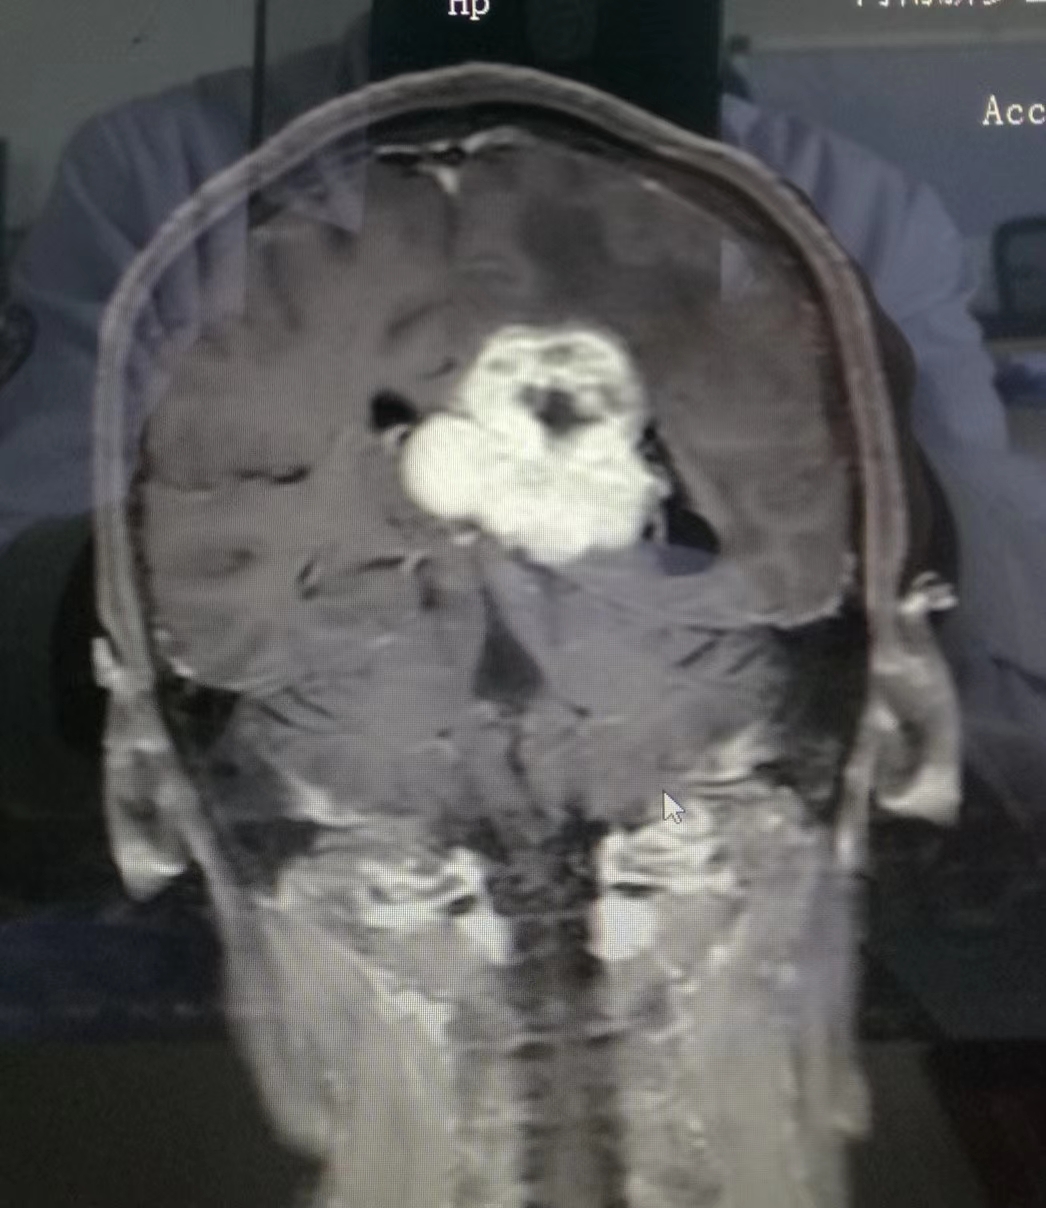

术前MRI